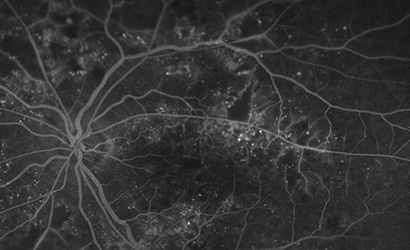

黄斑浮腫に対するナビゲーションレーザー

糖尿病黄斑症や網膜静脈閉塞症による黄斑浮腫に対して、ナビゲーションレーザーを使用する治療も行っています。国内ではまだ普及していないレーザー機器ですが、マニュアルでは困難な精度の高いレーザー照射ができ、新たな治療の可能性が期待されています。佐藤医師が国内有数の実績をつくり、学会や論文で多くの報告をしています。

糖尿病黄斑症のナビゲーションレーザー格子状光凝固と血管瘤への直接凝固の効果の比較

眼科臨床紀要 第15巻 第1号 22-27;2022、佐藤裕之ほか

網膜中心静脈閉塞の黄斑浮腫に対するNAVILASの効果

眼科手術 Vol.33 No.3 442-447;2020、佐藤裕之ほか